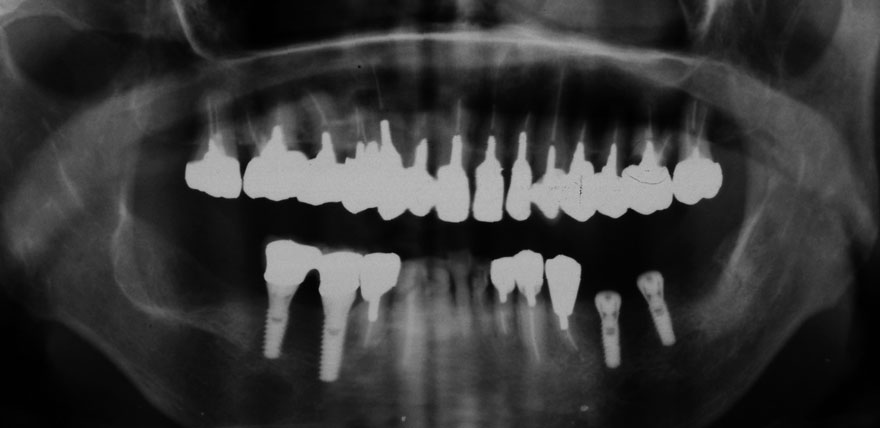

初診時 41歳 男性 平均歯槽骨喪失量:4.11mm

河田歯科医院

30年後 71歳

平均歯槽骨喪失量:3.70mm

30年間再生量:+0.41mm

年間再生速度:+0.014mm

(ケア頻度:1.27ヵ月ごと)